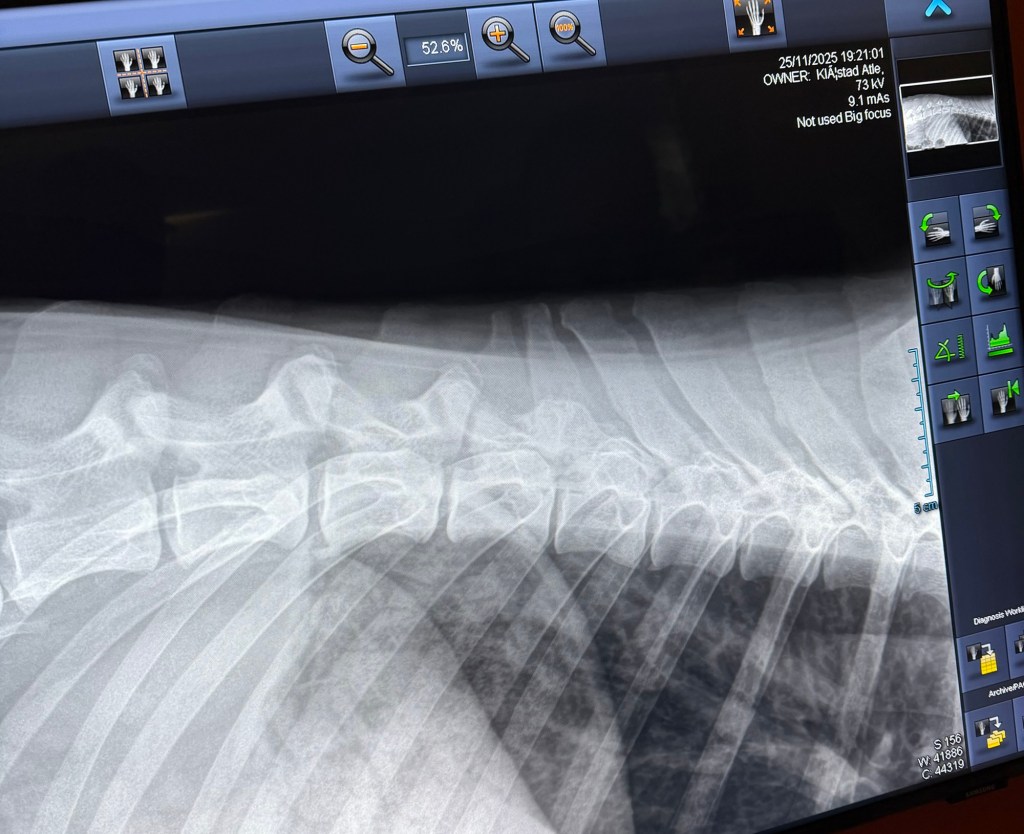

Freki har også vært på røntgen nå i november 2025, i en alder av 3år og 8måneder. Dette grunnet et ønske om å avdekke eventuelle svakheter eller forandringer i skjelett. Freki er en kraftig og stor hund med mye muskler og kraft, så her er det store påkjenninger. Rygg og albuer ble sjekket og resultatene var fantastiske og meget bra! Han har mikroskopiske forandringer i rygg og en flott bakpart med robust lende-rygg. Albuene er som tidligere, uten stor signifikant forandring. En frisk og sunn 4 åring! Freki har et utrolig flott vesen og er en ordentlig glad Bamse-gutt med masse kjærlighet til alle.